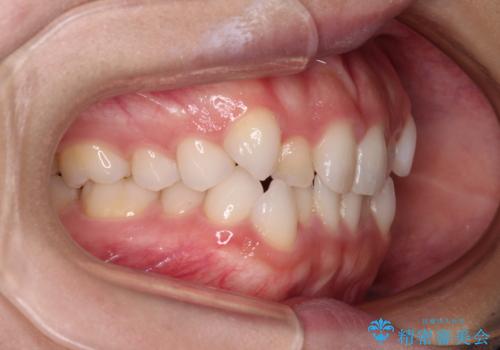

前歯のデコボコとクロスバイト ワイヤー装置での抜歯矯正

- 前歯のデコボコとクロスバイトを気にして来院された患者様です。

上下ともにデコボコはそれほど強くありませんでしたが、非抜歯では口元が突出した仕上がりとなる可能性があるため、上下左右の第一小臼歯4本を抜歯し、ワイヤー装置での抜歯矯正を行うこととしました

スペースを閉じるために期間を要しましたが、無事に綺麗な口元に仕上げることができました。